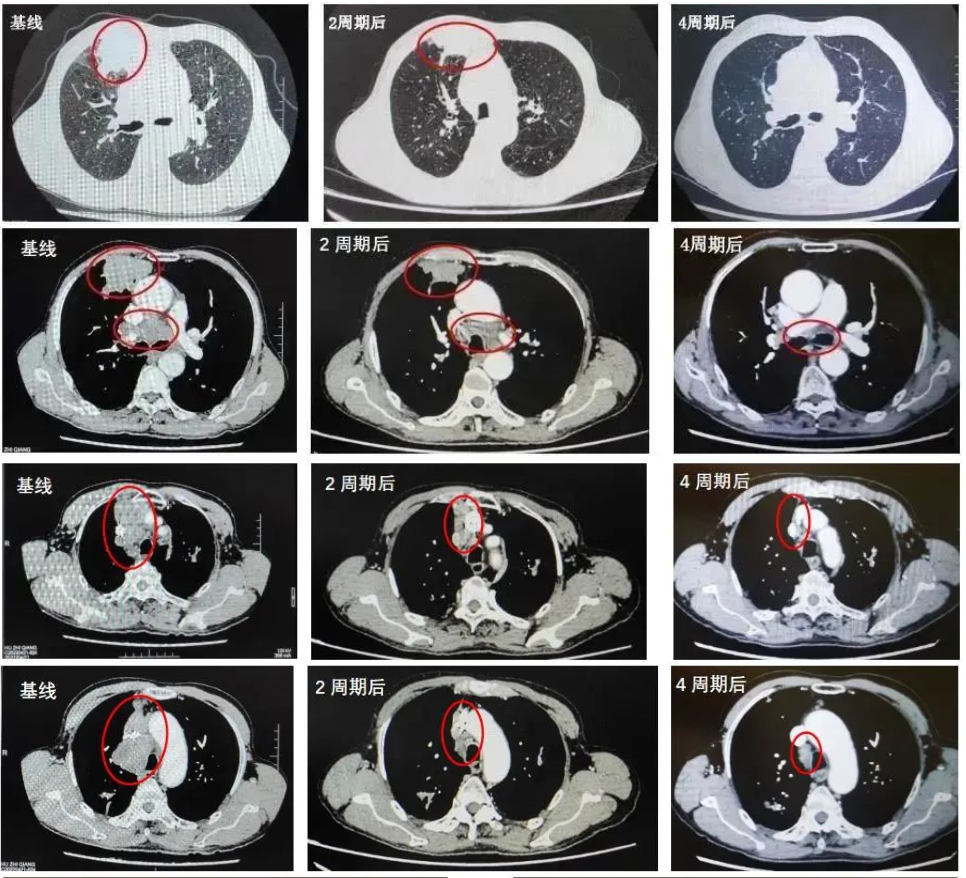

2022年5月11日-2022年7月30日:PD-1抑制剂+EC方案化疗共4周期,具体方案为:斯鲁利单抗(250mg,4.5mg/kg)+依托泊苷(0.16g d1-3)+卡铂(0.53g AUC5)。

2022年7月4日复查CT:与PACS20220421老片对比,现片示:1.右肺上叶前段不规则肿块灶(40mm×37mm)并纵隔多发肿大淋巴结明显缩小,上腔静脉受压变扁较前减轻:考虑周围型肺CA并纵隔淋巴结转移。2.双上肺、左下肺肺结核可能性大,CT表现为稳定性征象。3.慢性支气管疾患:肺气肿;肺大泡。

2022年7月5日复查脑部MRI提示:与PACS20220529老片对比,现片示:左侧颞叶强化灶较前稍缩小。

总体疗效评价为PR。

2022年8月23日复查CT:1.右肺上叶前段不规则肿块灶(40mm×36mm)并纵隔多发肿大淋巴结基本同前,上腔静脉受压变扁同前。2.双上肺、左下肺肺结核可能性大,CT表现为稳定性征象。3.慢性支气管疾患:肺气肿;肺大泡,基本同前。4.升主动脉扩张。

MRI:与PACS20220529老片对比,现片示:左侧颞叶强化灶较前稍缩小。

疗效维持PR。

该例患者为广泛期小细胞肺癌患者,合并陈旧性肺结核,初诊伴有脑转移。2022年ASCO大会口头报道的ASTRUM-005研究中斯鲁利单抗有很好的疗效和安全性数据6,依据《2022年CSCO小细胞肺癌诊疗指南》,该患者一线使用斯鲁利单抗联合EC化疗方案进行治疗,治疗后咳嗽、声嘶较前明显好转,体力状况明显改善,生活质量明显提升。肿瘤标志物出现明显下降,且影像学检查提示肿瘤病灶出现明显退缩,疗效显著,且在治疗过程中未出现结核复燃。治疗期间患者未出现不可控的免疫不良反应,安全性良好。

该患者是一个基线伴有脑转移的广泛期小细胞肺癌患者,《2022年CSCO小细胞肺癌诊疗指南》推荐,对于无症状的脑转移小细胞肺癌患者,一线治疗推荐免疫联合化疗后,再行全脑放疗。此患者在进行4个周期斯鲁利单抗联合卡铂依托泊苷治疗后,影像学提示病灶明显退缩,脑转移病灶也明显缩小,疗效达到PR,充分证明斯鲁利单抗在广泛期小细胞肺癌患者中的良好疗效。